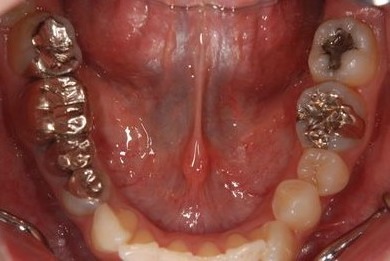

セラミックの症例写真 SHINBI

セラミック治療

| 治療内容 | オールセラミック4本(オールセラミック用土台4本)、メタルボンドセラミック2本(メタルボンドセラミック用土台2本) | ||||||||||||||||||||||||||||||||